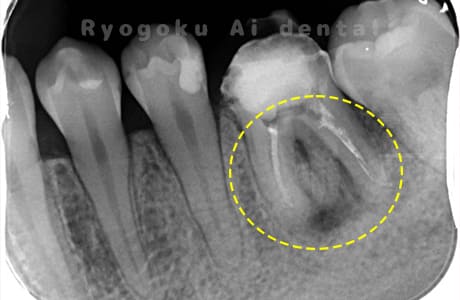

- 重度カリエス

- マイクロエンド

- 99,000円

虫歯が大きく、神経の保存ができなかったため、マイクロエンド治療を行いました。